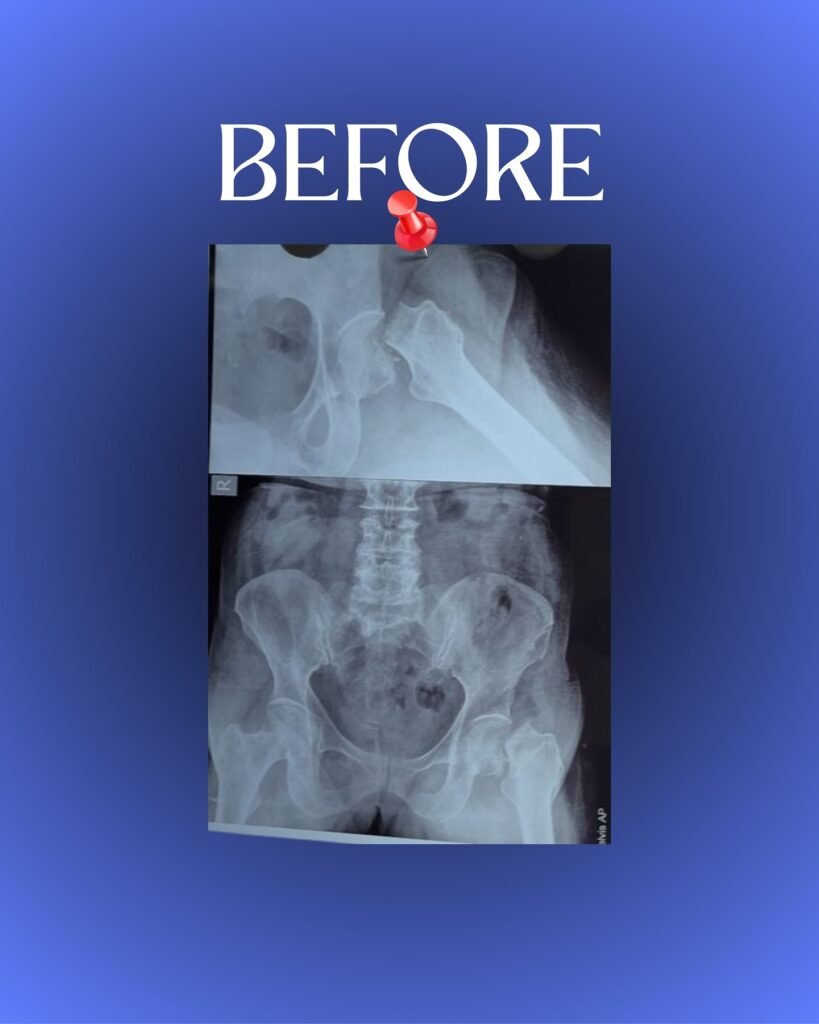

Before performing a hip replacement in Jabalpur, Dr. Nachiket Pansey carries out a detailed evaluation, including X-rays, MRI scans, and medical tests. This helps identify the extent of joint damage and allows him to design a personalized surgical plan. His careful approach ensures every patient receives the most suitable hip implant and achieves the best results from their hip arthroplasty.